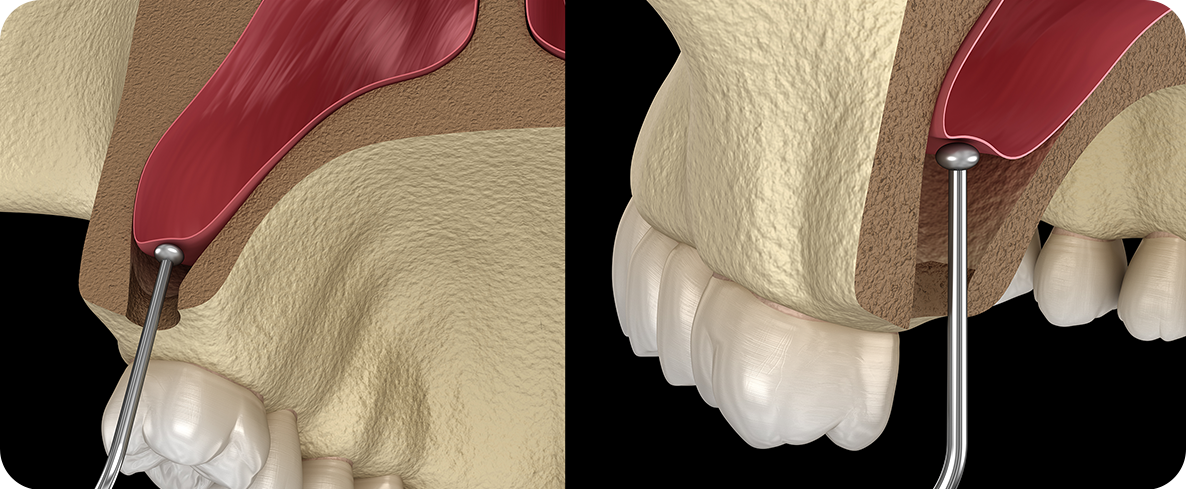

치조골 이식술 방법

일반 치조골 이식

치조골 흡수로 인해 임플란트를 식립할

잇몸뼈가 부족한 경우 뼈이식재를 이식한 후

골 형성을 유도하고 회복해

안정적인 임플란트를 진행합니다.

치조골 흡수로 인해 임플란트를 식립할 잇몸뼈가 부족한 경우

뼈이식재를 이식한 후 골형성을 유도하고 회복해

뼈이식임플란트 시술과정

잇몸뼈가 소실된 부위에 뼈 이식재를 이식하고

잇몸뼈를 보강한 후 임플란트 식립을 진행합니다.

잇몸뼈가 소실된 부위에 뼈 이식재를 이식하고 잇몸뼈를 보강한 후 임플란트 식립을 진행합니다.